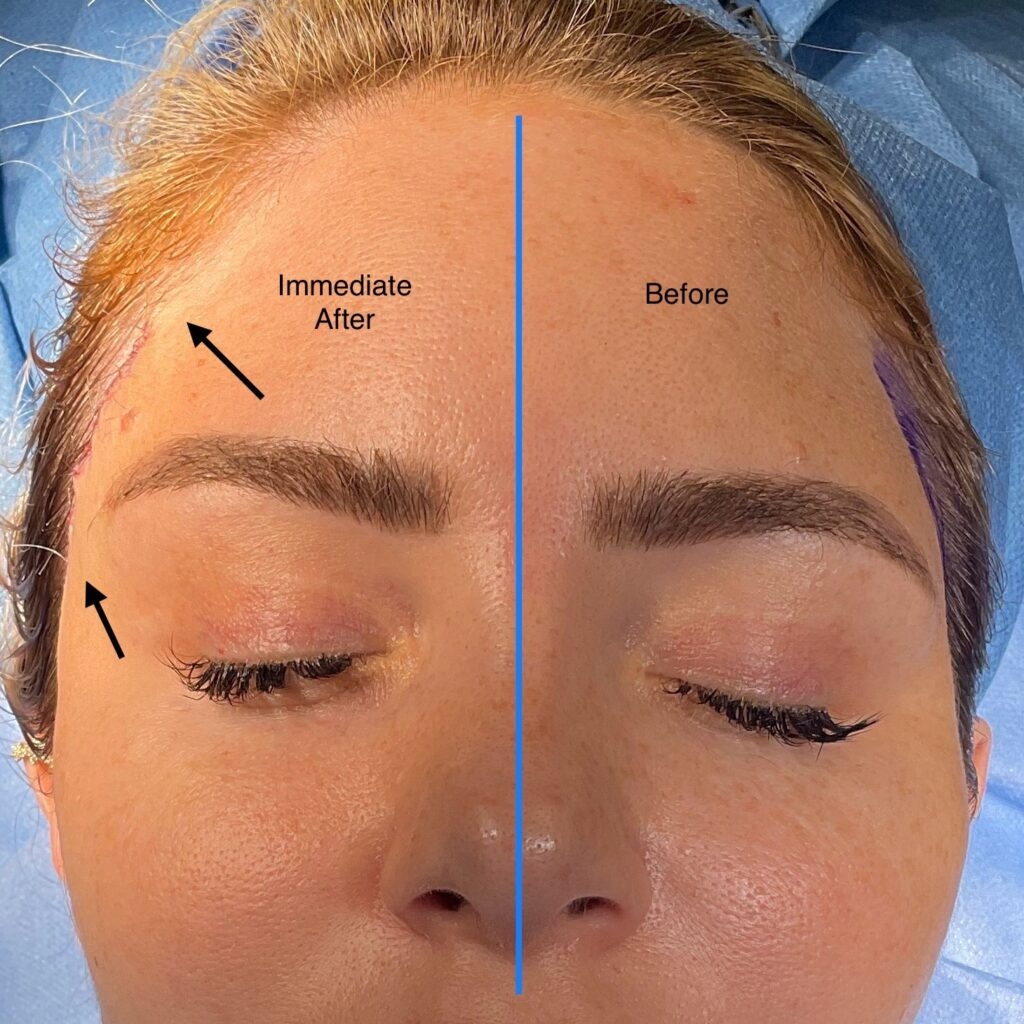

ENDOSCOPIC BROW LIFT BEFORE & AFTER

DIRECT BROW LIFT BEFORE & AFTER